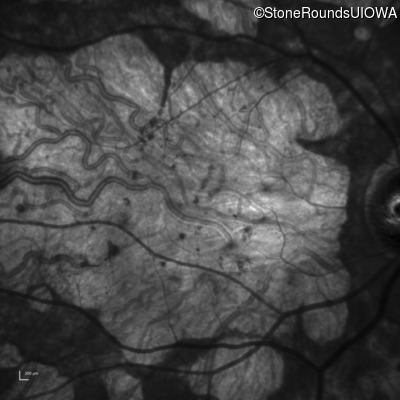

| AR Stargardt Disease | ABCA4 | Cys205Phe TGC>TTC | Gly863Ala (G)GA>(G)CA | AR |